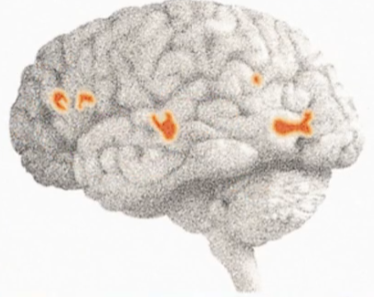

- 男女视觉皮质区回路的差异

图17-2 - 男生where回路较发达,女生what回路更发达

- 听悲哀的事情,男女大脑活化情况

图17-3 女生

图17-4 男生(男生分泌血清素的速度比女生快59%) -